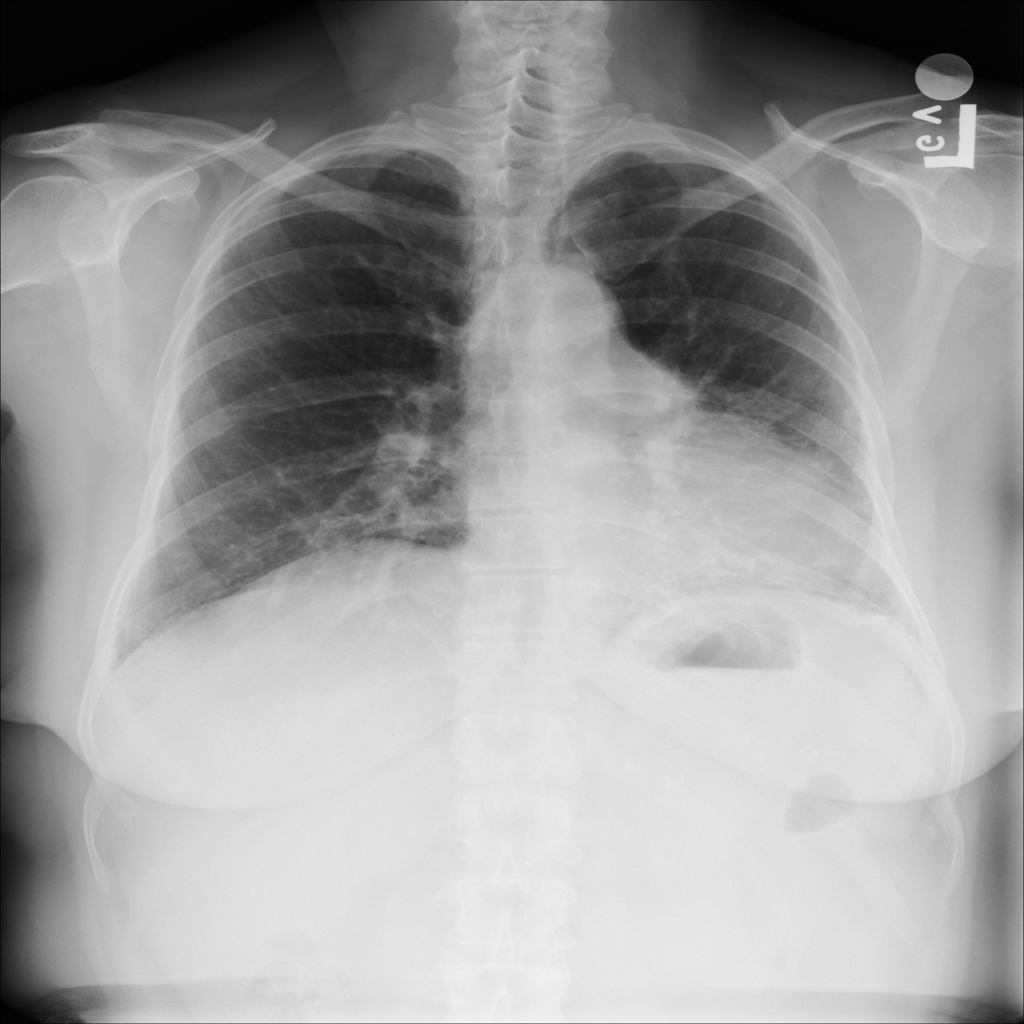

PAT-E066 · IMG-010Fibrosis

PAT-E066 · IMG-010

PA